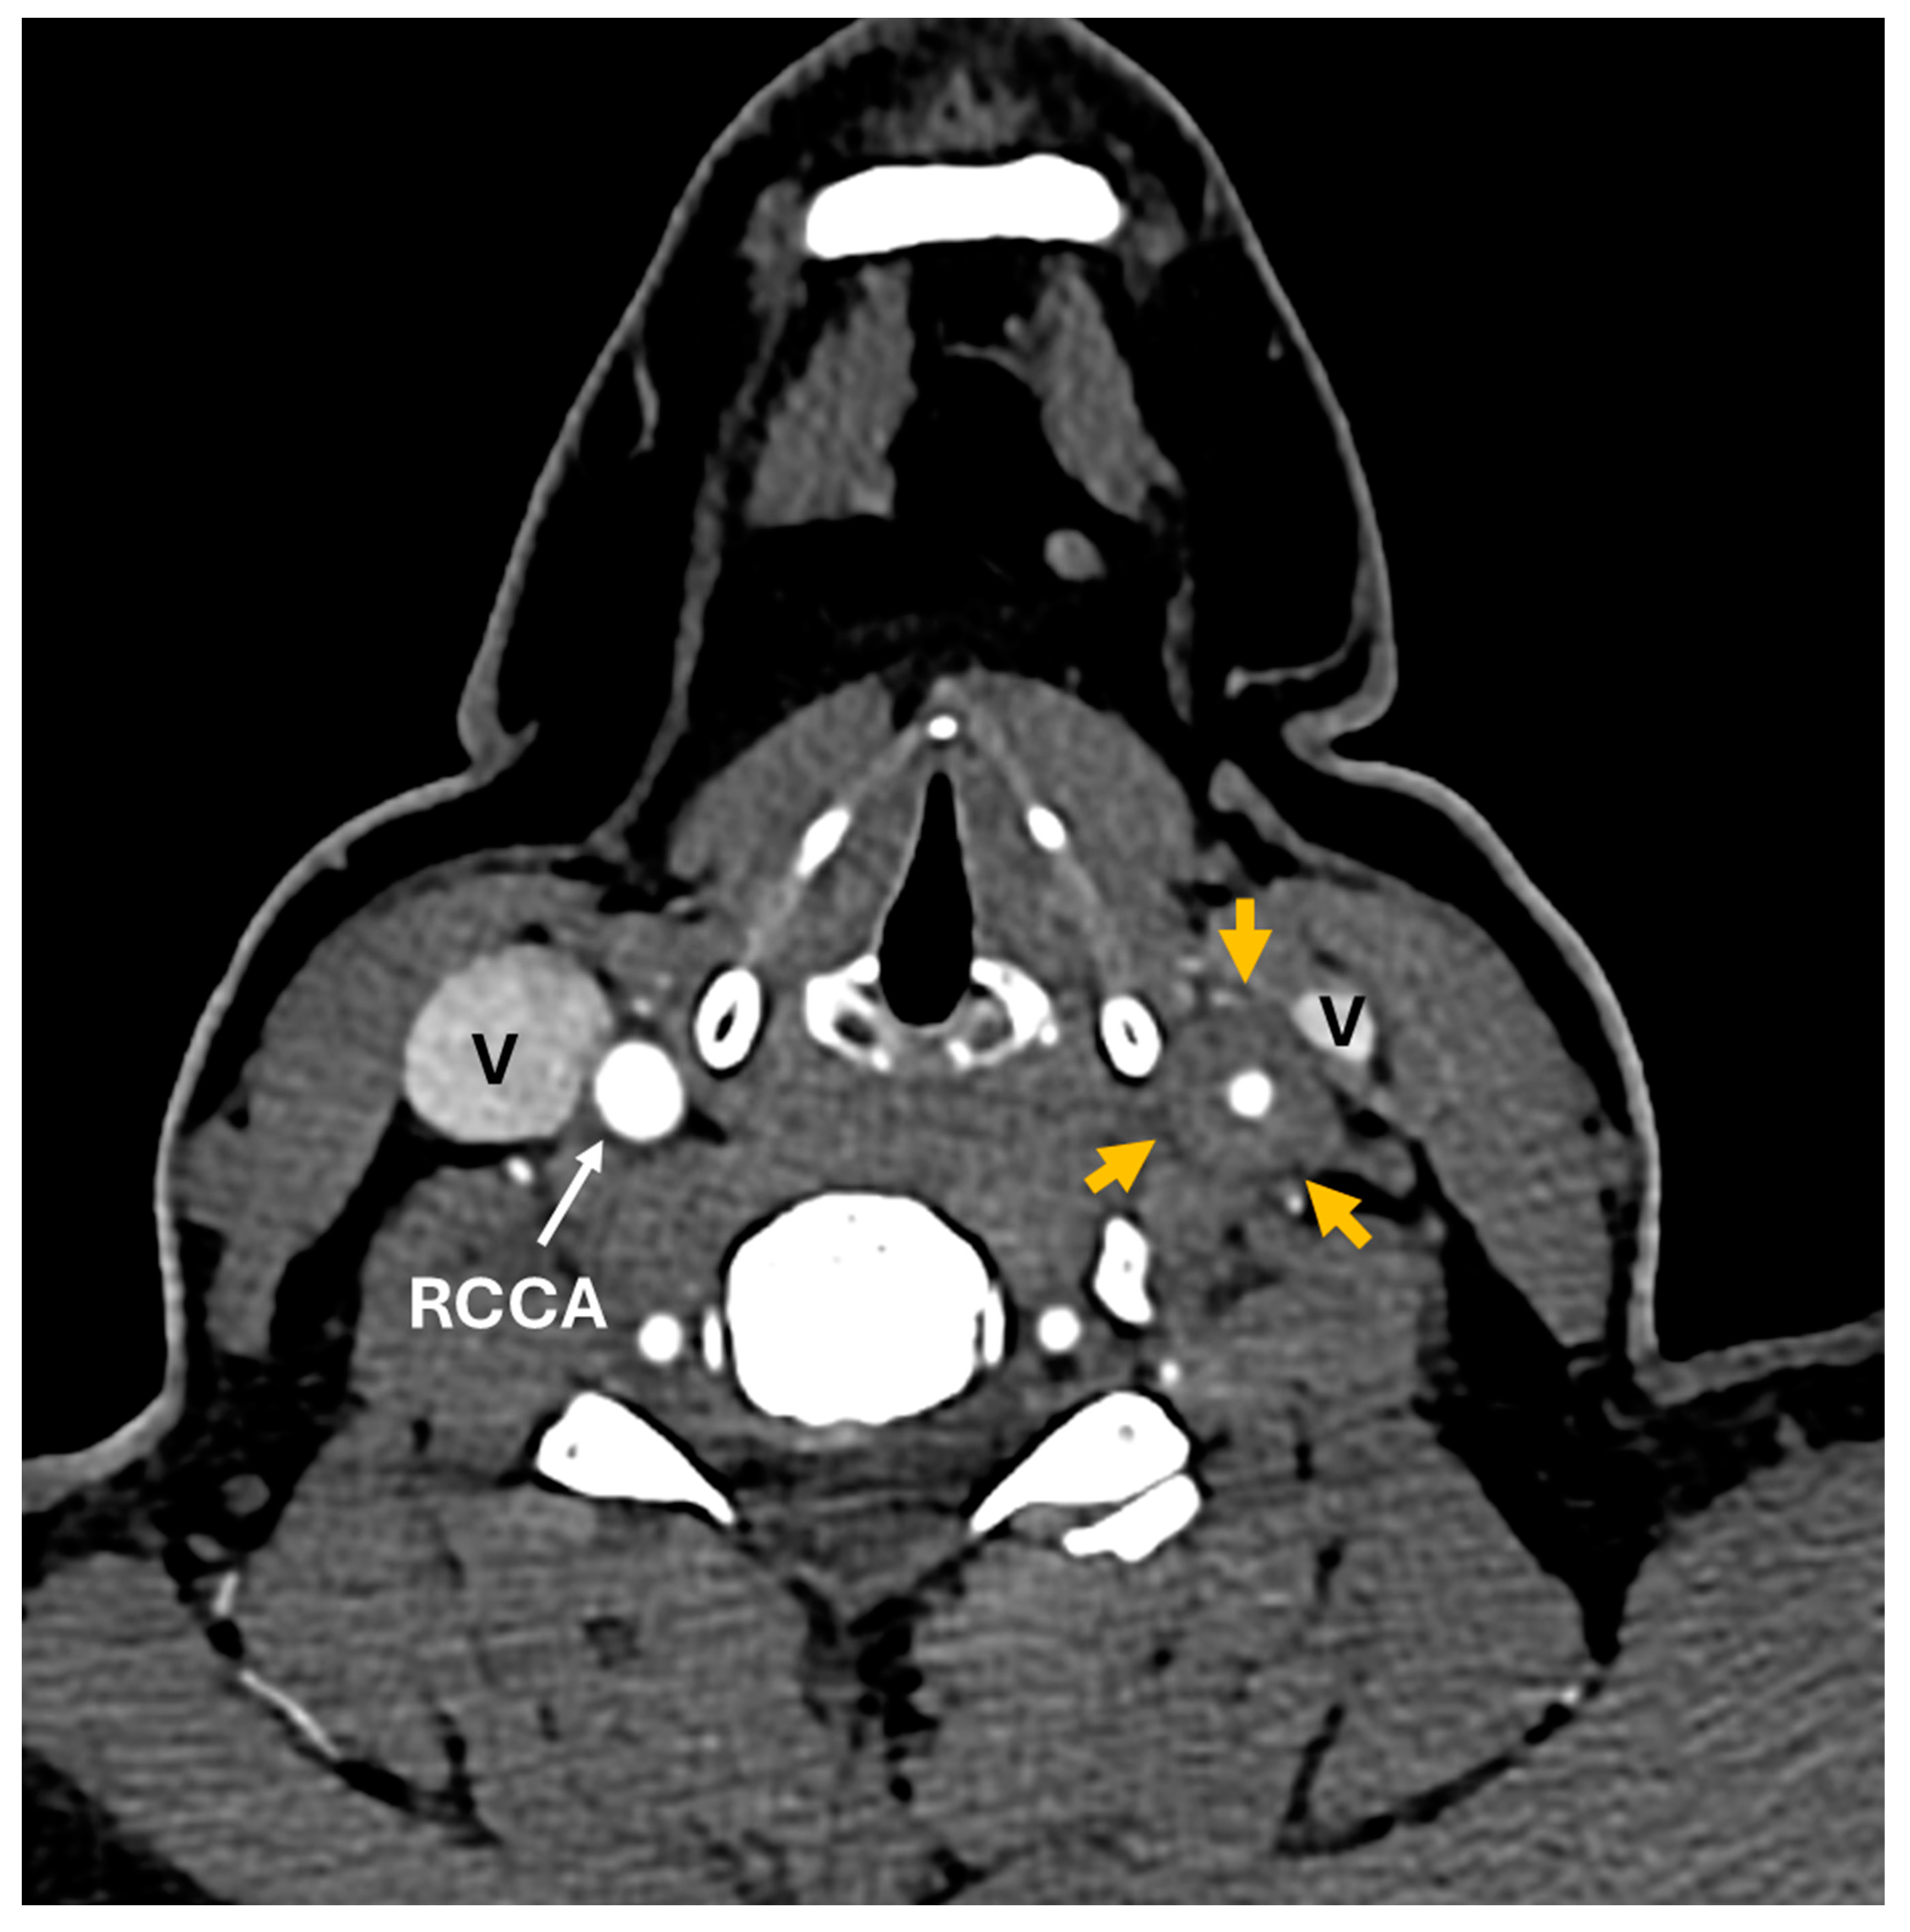

Figure 3. CT angiogram, axial images below the level of carotid bifurcation shows diffuse circumferential thickening of the common (CCA) and internal carotid artery (ICA) wall on the left side (orange arrows).

Figure 4. CT angiogram, axial images above the level of carotid bifurcation shows diffuse circumferential thickening of the common (CCA) and internal carotid artery (ICA) wall on the left side (orange arrows). Compare normal wall thickness of the right carotid artery. White arrows point out right common (RCCA) and internal (RICA) carotid arteries, and bilateral external carotid arteries (ECA). Internal jugular veins (V). Repeat CT neck angiogram with contrast revealed left-sided diffuse circumferential rim of soft tissue thickening involving the left carotid artery concerning for large vessel vasculitis. It is unclear how long the carotid bulb thickening had been present.

A 35-year-old woman with a prior history of left central retinal artery occlusion and bilateral sensorineural hearing loss concerning initially for neurosarcoidosis (never histologically proven) presented for clinic follow-up. She had a complicated disease course dating back many years involving different specialists including fluctuating hearing loss partially responsive to corticosteroids necessitating cochlear implants and developed central retinal occlusion of the left eye (Figure 1 and Figure 2). This was concerning for possible underlying inflammatory condition such as neurosarcoidosis or Susac syndrome (MRI atypical sans corpus lesion) and she received IV immunoglobulin treatment. When she returned for follow-up, she had complaints of episodes of confusion, but quiescent symptoms without visual change, status post adalimumab and methotrexate addition. She sought emergency care for new transient arm numbness and confusion and CTA neck revealed carotid bulb circumferential thickening suggestive of vasculitis (Figure 3, Figure 4 and Figure 5). The patient was initiated on Infliximab with IV methylprednisolone and close follow-up with neurology and vascular medicine for management of Takayasu arteritis.